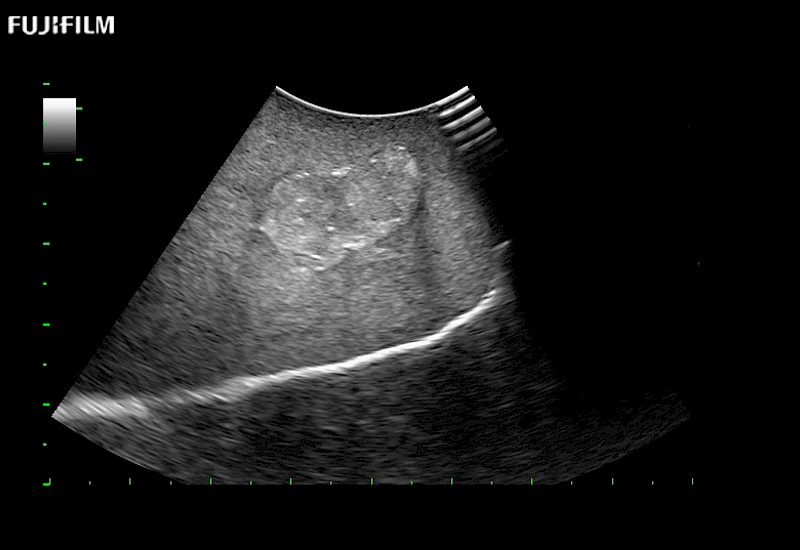

Our dedication to Surgical Oncology allows us to offer superior image quality, outstanding system reliability and intuitive use of cutting edge technology.

The ARIETTA 750 incorporates all of the proven technologies and functions that medical professionals have come to expect from Fujifilm Healthcare.

ARIETTA 750 is the definitive diagnostic ultrasound solution for any clinical setting - Private Office, Imaging Center, or Hospital. The ARIETTA platform provides the ultimate in clinical performance with its state-of-the-art features and large user-friendly display.

The ARIETTA 650 DI combines trusted Fujifilm Healthcare technologies and features tailored for surgical oncology.

Designed to meet the demands of surgeons, the ARIETTA 650 DI offers precise guidance. Its advanced capabilities and large, intuitive display offer accurate and efficient care in operating rooms and specialized surgical settings.